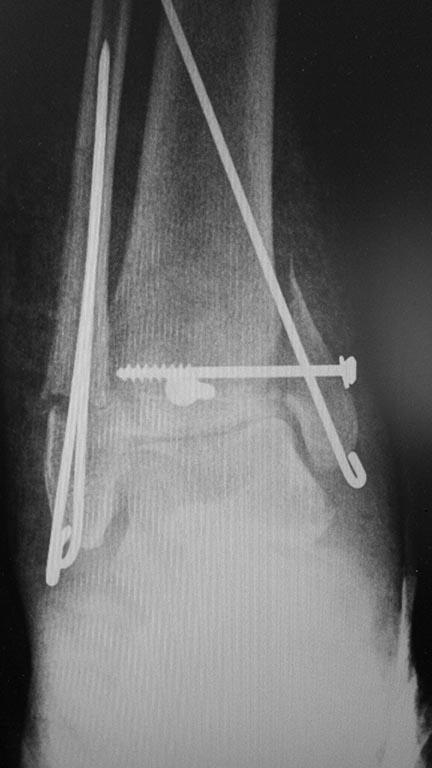

Операция 10.2014: закрытая репозиция, остеосинтез спицами,

винтами. В дальнейшем произошло ожидаемое усугубление нарушений

взаимоотношений в голеностопном суставе.

Какой план лечения,на Ваш взгляд, предпочтительнее в данном случае?

Возможно ли одномоментно устранить подвывих или только на аппарате

Иллизарова? Первичные снимки после травмы отсутствуют. Критично ли

"растоптана" латеральная суставная поверхность большеберцовой кости?